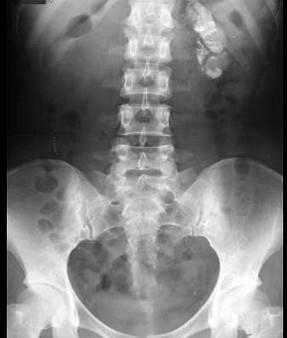

关于临床肾结核的病理特点哪项不正确 ( )A、钙化形成肾结石B、干酪样脓肿C、空洞性溃疡D、“肾自截”或“自家肾切除”E、脓肾

问题 关于临床肾结核的病理特点哪项不正确 ( )

选项 A、钙化形成肾结石 B、干酪样脓肿 C、空洞性溃疡 D、“肾自截”或“自家肾切除” E、脓肾

答案 A